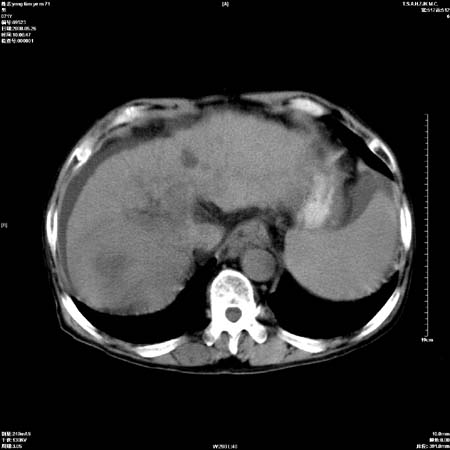

以下是引用医影拾贝在2008-6-5 22:48:00的发言:[br]肝硬化、门脉高压、胃底食管静脉曲张、低蛋白血症(胆囊壁水肿、增厚)、腹水[br]脾功能亢进、脾大、脾、左肾囊肿[br]肝囊性占位、不除外肝脓肿可能[br]建议增强以除外肝右叶肝ca可能

以下是引用chenglinhunan在2008-6-5 22:53:00的发言:[br]1. 肝硬化腹水,脾肿大。[br]2. 肝右后叶占位,肝癌。[br]3。建议ct增强扫描。

以下是引用xulianj在2008-6-5 21:40:00的发言:[br]支持肝硬化腹水;建议增强。肝、脾、肾囊肿待排。

以下是引用zjzjr在2008-6-6 12:34:00的发言:[br]1. 肝硬化腹水,脾肿大。[br]2. 肝右后叶占位,肝癌。[br]3。建议ct增强扫描。[br]4肝脾囊肿.